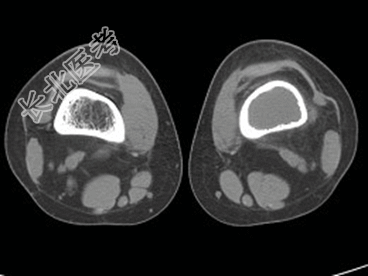

- [材料题] 患者,男,33岁,左股骨肿块半年余,无明显症状,查体一般情况良好。

- 简答题1、结合所提供的图像,该患者诊断为?